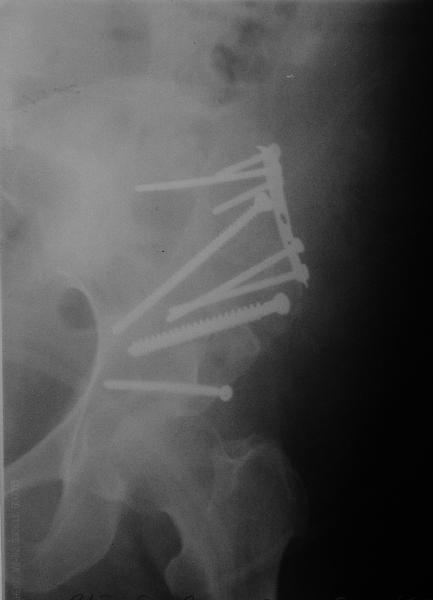

Выполнена реконструкция крыла левой подвздошной кости, грыжесечение через подвздошно-бедренный доступ. 2 фрагмента подвздошной кости, грыжа выходит между ними (см. картинки). Грыжевой мешок, спаянный с ПЖК, подвздошной костью, вскрыт, его содержимое (петли кишечника) вправлено в брюшную полость. Грыжевой мешок выделен, иссечен, наложены два ряда отдельных швов на брюшину. Отломки подвздошной кости стянуты друг с другом, зафиксированы 1/3-трубчатой пластиной и винтами к телу подвздошной кости (см. рентгенограммы). Дефект подвздошной кости был закрыт практически полностью. Решено не применять сетку. Иссечен лоскут истонченной кожи 15 на 8 см.